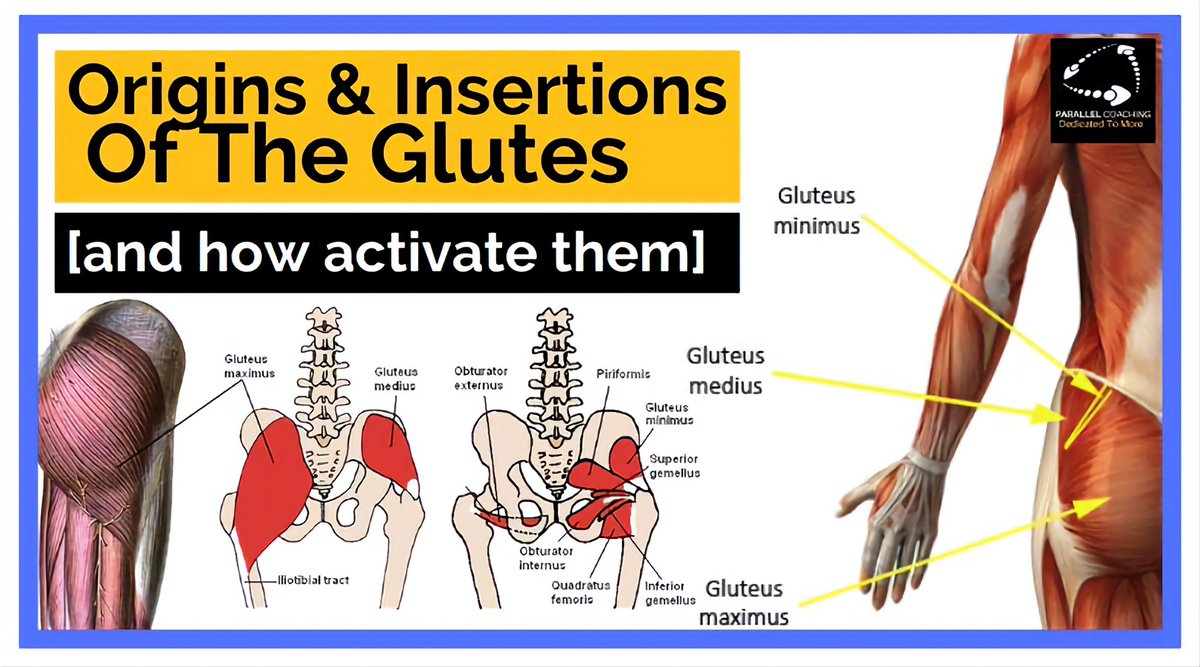

فين يكون منشأ العضلات الخلفية للرجل وخصوصا المعروفة بال Glutes وهي ( عضلات الأرداف) وأيضا عضلات ال piriformis وهي ( العضلة الكمثرية ). ⁉️

فين يكون منشأ العضلات الخلفية للرجل وخصوصا المعروفة بال Glutes وهي ( عضلات الأرداف) وأيضا عضلات ال piriformis وهي ( العضلة الكمثرية ). ⁉️